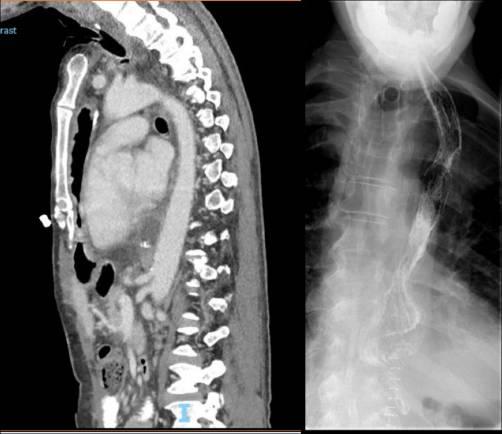

钡剂吞咽荧光镜检查报告食管道不规则,吞咽时吸入造影剂,并发现食管肿块(图1)。颈部、胸部、腹部和骨盆的计算机断层扫描(CT)显示食管壁增厚,表明食管和近端气管之间存在瘘管,以及感染引起的双侧磨砂玻璃阴影(图2)。值得注意的是,初次报告中没有提到异物。食管胃十二指肠镜(OGD)对距离切牙19厘米处的肿块进行了评论,显示在此水平上有一个“大的、有柄的息肉”样病变,很难进行组织活检。

图2 CT扫描的轴向切片与对比。显示T2椎体水平气管食管瘘管内从食管延伸到近端气管的线性高密度阴影